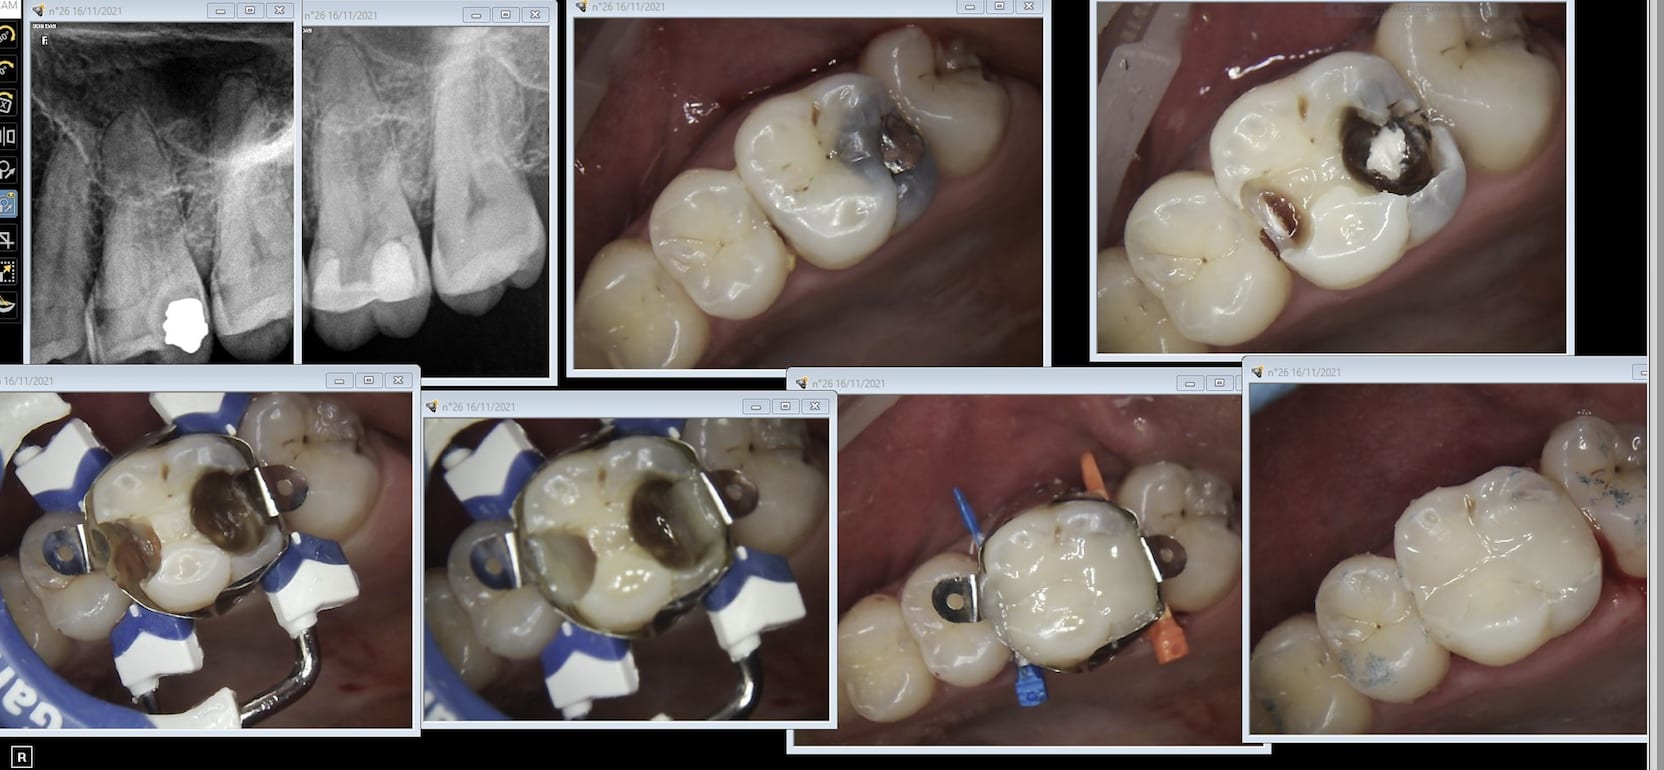

Bon alors en fait je ne me suis pas mis à l'implanto ni à l'ortho parce qu'en ne faisant qu'une dentisterie de base je payais déjà trop d'impôts et que ça m'emmerdait d'en payer encore plus et puis j'avais autre chose à foutre ( jet ski, bateau, quad kite surf et fiestas le WE avec les potes d'ailleurs on surnommait le jet ski "la machine à décuiter" après beaucoup trop de bières ingurgitées à Camaret sur mer ou à Molène et Ouessant une fois j'étais même rentré blindé de molène à Brest à minuit pas compliqué tu laisses toutes les cardinales Nord à tribord puis cap sur phare de st Matthieu puis phare du petit minou phare du Portzic et t'es arrivé ca ne fait que 50 bornes....). Il n'y a plus de fiestas de jet skis mais je ne fais toujours pas d'implanto ni d'ortho et quasiment pas d'onlays. Tiens amalgame vieux de 18 ans le patient en a 36 refait cet aprèm avec petit coiffage direct. Combien de temps ce sous traitement et cette perte de chances va durer ça va durer? hein ?